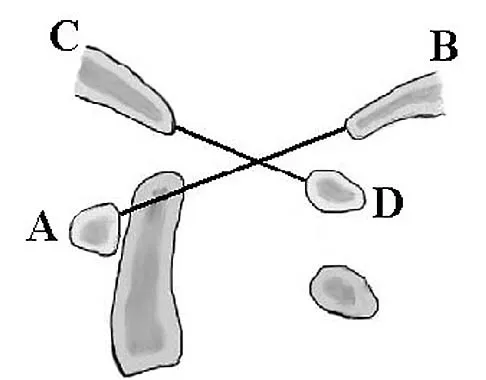

In Figure 49, line AB connects the anterior arch of C1 to the posterior margin of the foramen magnum. Line CD connects the anterior margin of the foramen magnum to the posterior arch of C1. What is the normal ratio of displacement from CD to AB (Power's ratio)?

Explanation